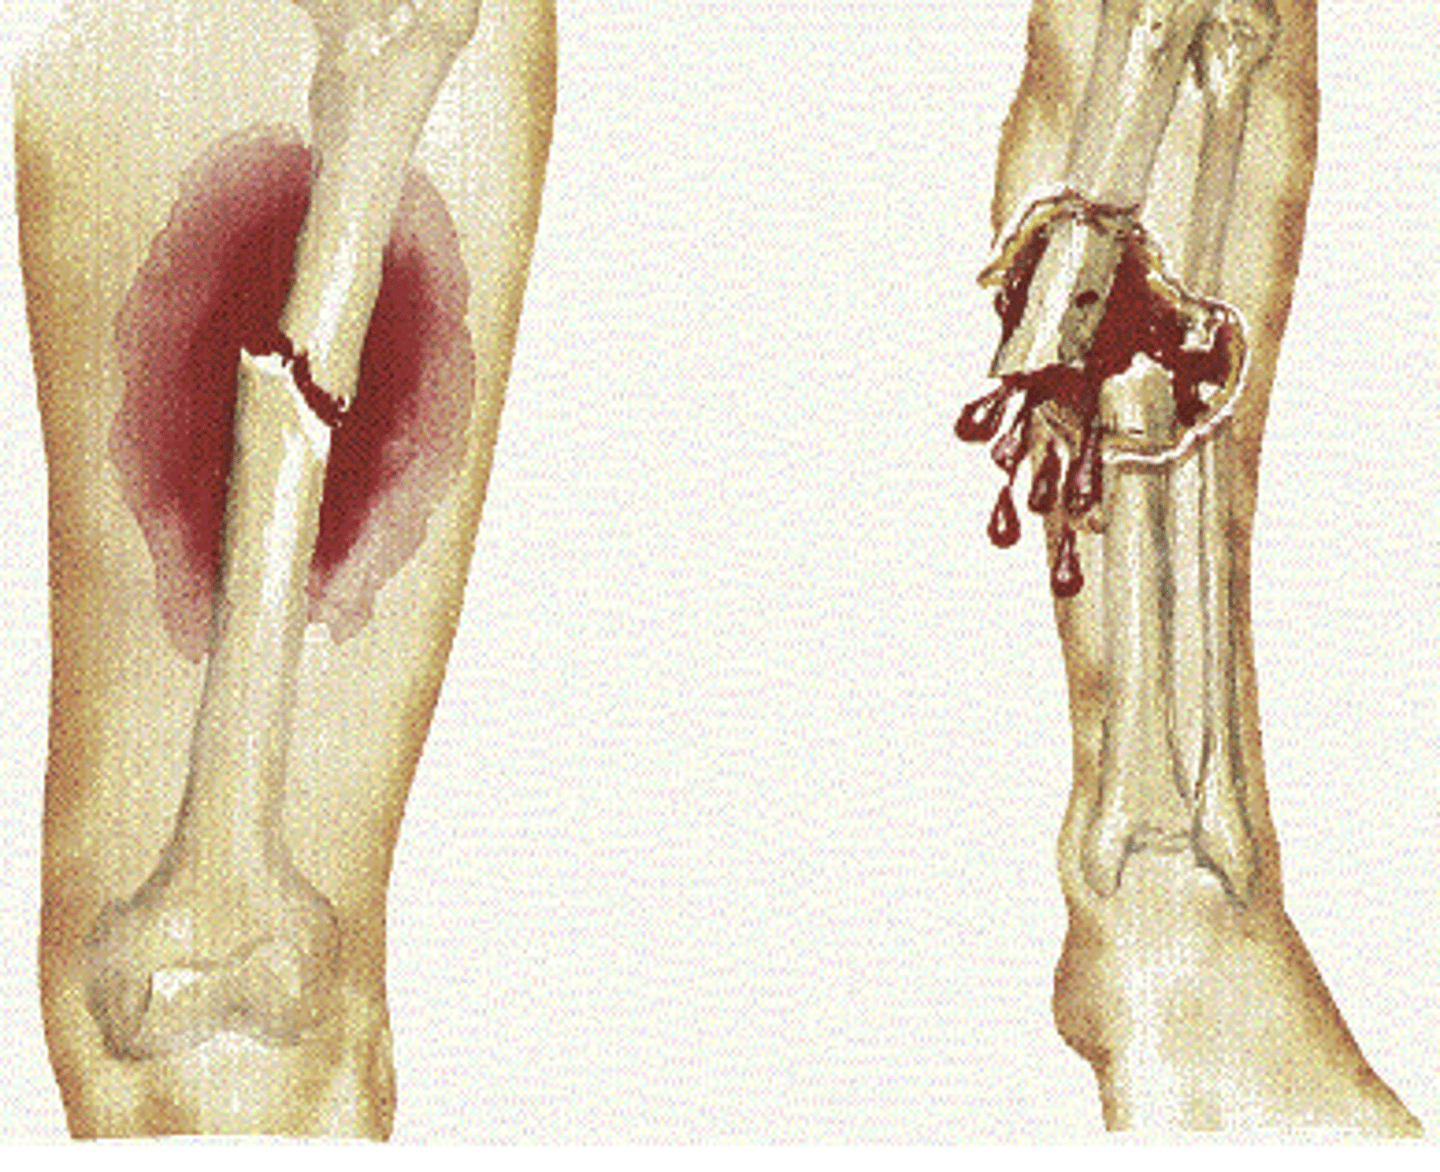

hematogenous osteomyelitis

A: Systemic infection spreads to bone

B: Purulent exudate collects as infection spreads, shearing off perforating arteries

C: Bone necrosis; necrotic bone separates from live bone to form devascularized fragments, called sequestra

D: Catch it early, long term consequences are relatively rare (less than 1-10%) – but include increase in fracture, development of chronic or reoccurring infection